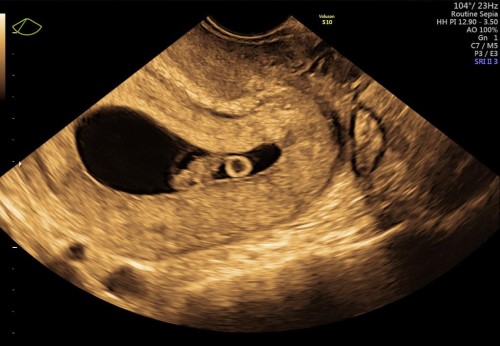

Realizamos ultrasonidos fetal avanzado desde el primer trimestre como el USG genético, USG estructural (sem 18-22) y estudios de bienestar fetal con tecnología Doppler para medición de flujos sanguíneos fetales como arteria umbilical, cerebral media, ductus venoso y en la madre las arterias uterinas.